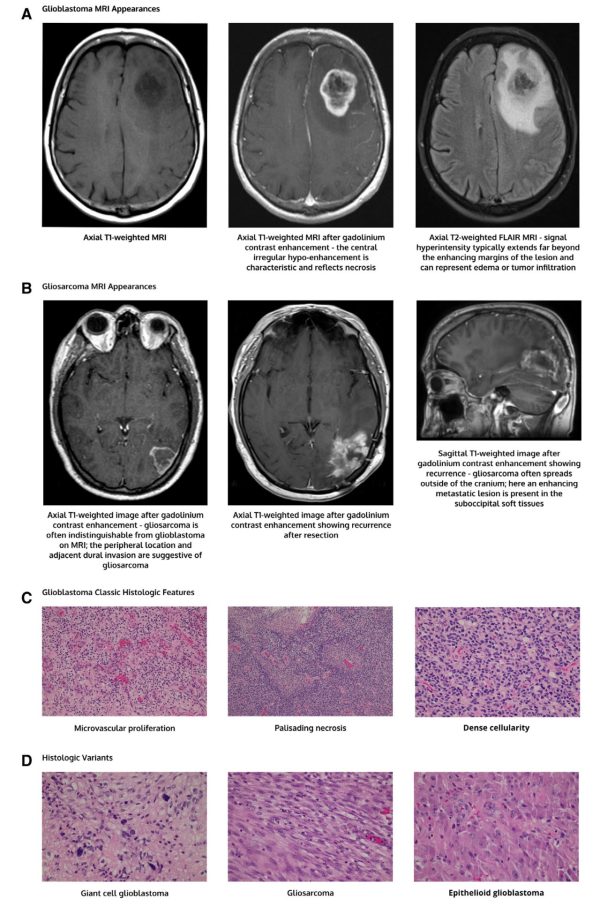

组织学形态上,两种GBM亚型都存在高级别星形细胞瘤的特征,有微血管增生、局灶坏死(图1)。在IDH野生型GBM中,还存在一些不同的组织学亚型。巨细胞胶质母细胞瘤含有大的、多形性、多核巨细胞。胶质肉瘤可见高级别恶性星形细胞瘤特征和肉瘤样间质化生。上皮样胶质母细胞瘤是一类新认定的亚型,肿瘤细胞具有的上皮样形态,近半数出现BRAF V600E突变。尽管如此分型,但是目前并没有根据组织学亚型调整治疗建议。GBM和胶质肉瘤的经典MRI如图1。巨细胞胶质母细胞瘤及上皮样胶质母细胞瘤没有可靠的影像学特征进行鉴别。